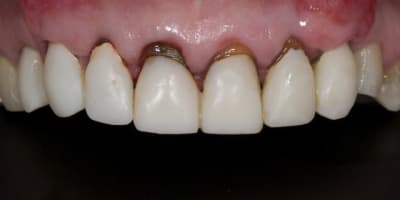

Alors j'ai commencé le traitement:

-ext 24 car mobilité type 2 + implant immédiat + couronne prov. en sous occ.

-Démontage difficile des ccm, mais surprise, traitement endo relativement mou et donc a priori pas trop délicat a reprendre.

-couronnes prov.

Aujourd'hui a 4 semaines:

A suivre reTR + moignon compo + tenon fibré + nouvelles prov dans les prochaines semaines.